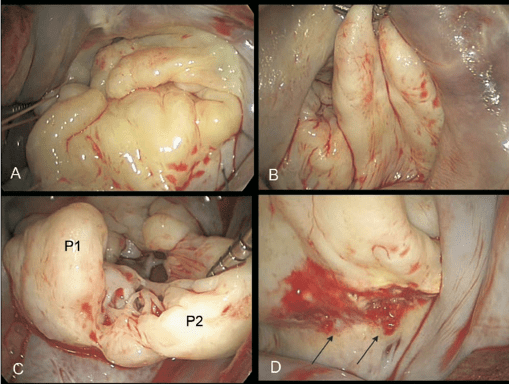

A degenerative mitral valve disease in which myxoid infiltration of the valve results in a myxomatous-appearing valve where the hallmark is excess thickened leaflet tissue

What is Barlow’s disease?